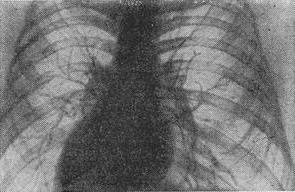

![]() Рис. 2. Рентгенограма грудної клітини в нормі. Пряма (передня) проекція. |

При лабораторно-інструментальному обстеженні досліджують мокротиння (див.), проводять рентгеноскопію, рентгенографію (рис. 2), бронхографию (див.), флюорографію (див.) в залежності від показань.